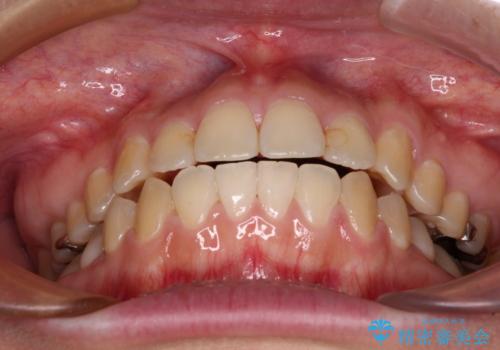

デコボコはあっという間に改善されましたが、開咬の改善に時間がかかりました。

舌の突出癖改善のトレーニングをしっかりと行っていただき、上下前歯が接触する咬み合わせを達成することができました。